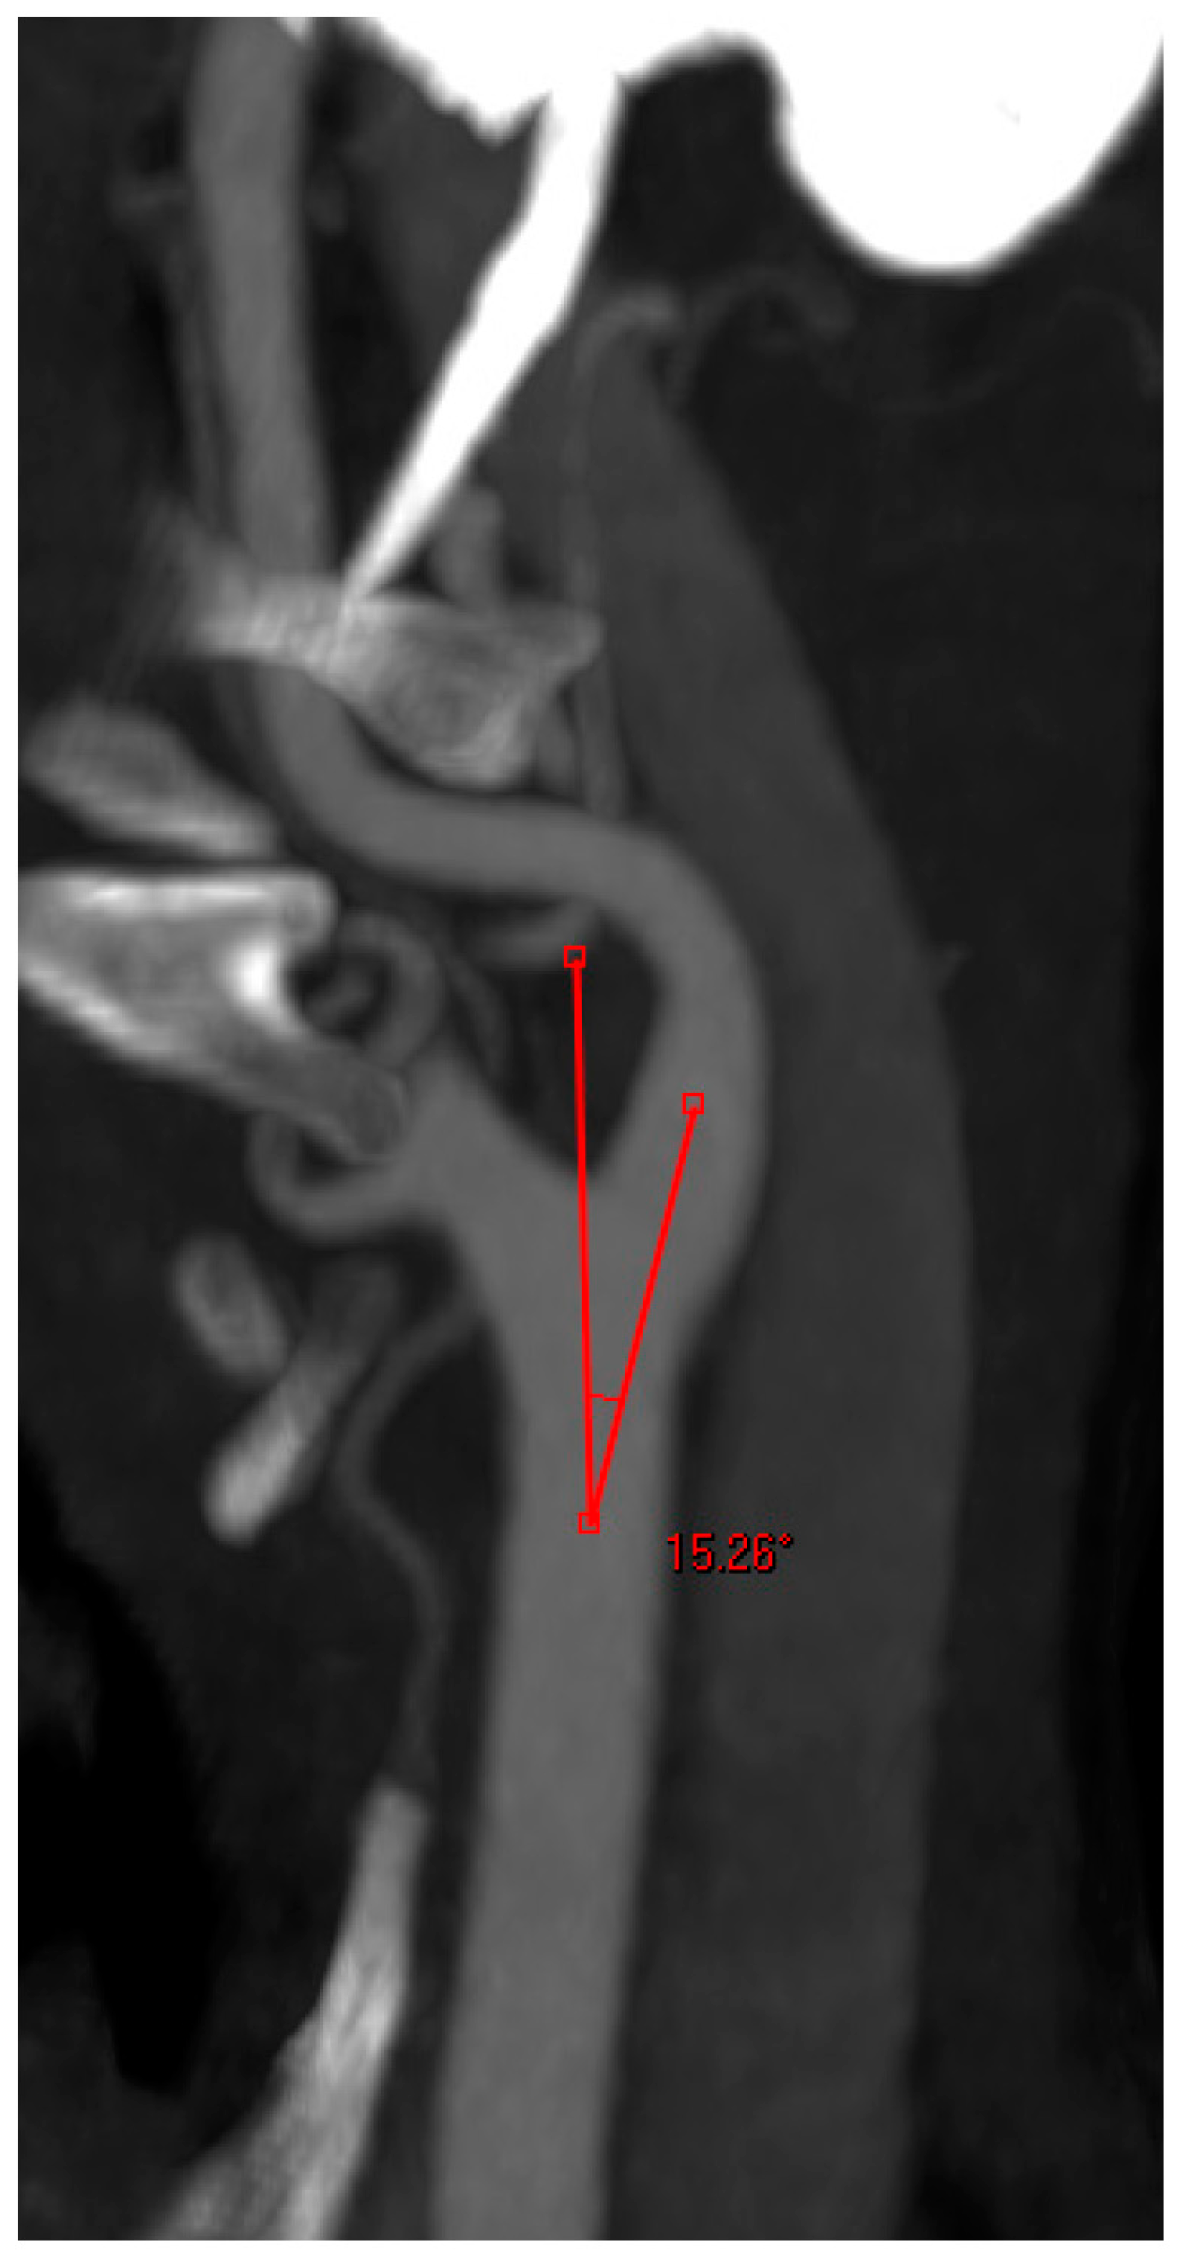

- Angle between the CCA and the ICA: measured on the treated side only. At the carotid bifurcation, one arm of the angle was placed along the central axis of the CCA and the other arm was drawn into the central axis of the ACI. The cranial angle was measured (Figure 4);

Figure 4. Angle measurement at the carotid bifurcation.

At the level of the carotid bifurcation, the angle between the CCA and ICA also plays an important role. Various studies support the statement that an obtuse angle at the carotid bifurcation can lead to a more difficult and risky cannulation of the ICA [25,26]. A subanalysis of the EVA-3S trial demonstrated that CAS interventions in patients with an angle >60° at the carotid bifurcation were associated with significantly higher complication rates [26]. An angle >60° was an exclusion criterion in this study. Our mean angle at the carotid bifurcation laid much lower than this value, and according to our experience an angle >60° at this level is relatively rare to find.